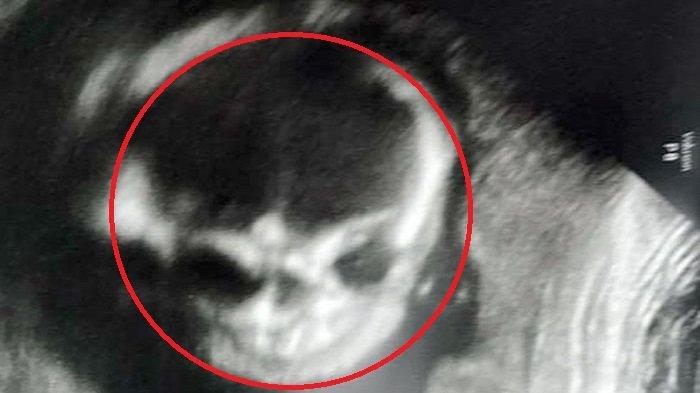

Ibu ini rasakan ketakutan ketika ditunjukkan gambar hasil dari pemindaian ultrasonic pada bayinya ketika berumur 21 minggu di dalam kandungan.

Menurut laporan Daily Mirror dikutip dari Intisari, pada Senin (12/8/19), Jessica Woods (23) asal Oklahoma, AS, mendapati bayinya terlihat hanya memiliki kerangka melalui hasil pemindaian ultrasonic.

Padahal wkatu itu usia kehamilannya sudah menginjak 21 minggu lima hari, yang termasuk cukup tua.

Bayi itu tampak seperti kerangka pada hasil ultrasonic yang ia bagikan.

Hal ini membuat sang ibu ketakutan akan apa yang terjadi pada anaknya saat setelah lahir.

Ibunya tak menyangka kondisi anak dalam kandungannya terlihat mengerikan.

Hingga akhirnya setelah dilahirkan kecemasan Jessica terobati dan hanya bayangan kosong belaka.

Saat melahirkan, dia merasa gugup karena khawatir dengan kondisi putranya, setelah melihat hasil ultrasonic yang ia lakukan.

Namun, setelah dilahirkan tampak seorang bayi laki-laki yang sempurna, dan kecemasan Jessica terjawab.

Jessica mengatakan, "Awalnya saya hanya melihat USG normal, dan semuanya baik-baik saja.".

"Tapi kemudian dia perlahan memutar kepalanya dan menghadap kami, itu benar-benar menyeramkan," katanya.

"Saya sedikit gugup dan cemas, tentang apa yang saya bayangkan ketika melahirkan anakku.". lanjutnya.